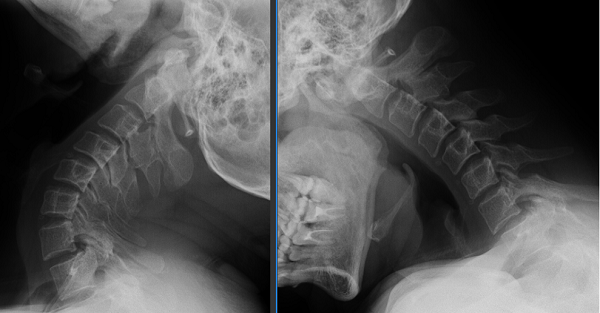

针对贾先生的病情,骨外一科柏涛主任团队进行了细致地讨论,个性化制定了贾先生的围手术期管理、手术方案包括:寰枢关节脱位复位技巧、固定节段的选择、植骨方式的选择。最终决定采用北医三院王超教授发明的方法:大重量牵引、压板复位、钉板系统固定、取自体髂骨进行中线植骨施行手术。

手术由柏涛主任医师、王国著副主任医师、董谐主治医师联手操刀,麻醉和护理团队全程精准护航,整个手术过程配合默契,术中失血量较少,最终圆满完成。麻醉苏醒后,贾先生意识清楚、对答切题、四肢活动正常。当看到贾先生能跟随手术医生的指导进行四肢的活动检查时,大家犹如面对强大的敌人打了一场胜仗,心中满是喜悦之情。

寰枢关节脱位,这种疾病隐匿性强,早期症状容易混淆,但若拖延不治,可能压迫神经血管,严重时甚至导致瘫痪、危及生命。此前,不少患者因当地医疗条件限制,不得不远赴外地求医。玉溪市人民医院骨外一科成功引入世界领先的由颅椎外科王超教授发明的手术技术,通过进修学习、王超教授亲临会诊手术、独立自主完成手术的路线,目前已为来自普洱、曲靖、楚雄及玉溪本地10余位患者成功开展了寰枢关节脱位手术。